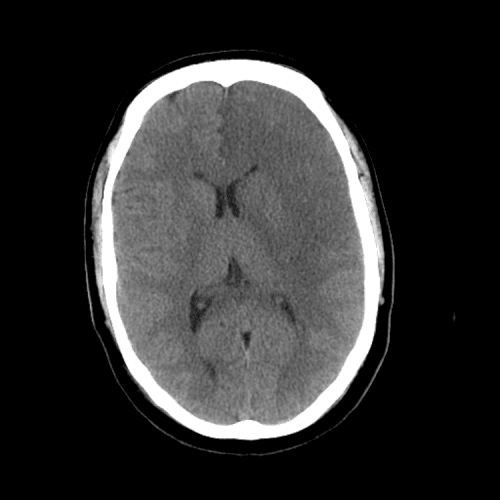

- Dense MCA sign

- Blurred basal ganglia sign